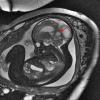

NEOPLASMS (EMBRYONAL)

ATRT - Atypical Teratoid Rhabdoid Tumor (6)